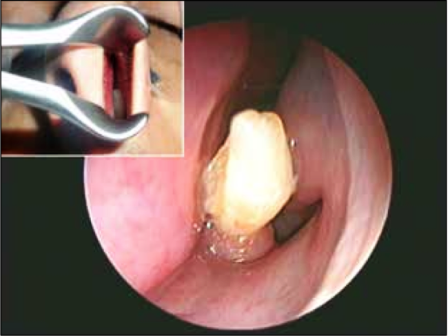

Vụ việc hi hữu xảy ra đối với một thanh niên ở A-rập Xê-út khi các bác sĩ phát hiện thấy một chiếc răng mọc bên trong lỗ mũi của anh này sau một thời gian dài chịu đựng những đợt chảy máu mũi bất thường.

Trong suốt ba năm liền, người thanh niên 22 tuổi (được giấu tên) phải chịu ít nhất một lần máu mũi chảy bất thường mỗi tháng. Sau khi đi đến bệnh viện khám, các bác sĩ bất ngờ phát hiện một chiếc răng mọc bên trong lỗ mũi của anh.

Báo cáo nghiên cứu do Tạp chí “Case Reports” được xuất bản ở Mỹ cho biết, đây là một chiếc răng khôn, thay vì mọc trong miệng thì nó lại nổi lên ở lỗ mũi gây nên hiện tượng chảy máu mũi.

Theo tờ Live Science, các bác sĩ ở bệnh viện quân y King Fahd tại Dhahran, Ả-rập Xê-út đã rất ngạc nhiên khi phát hiện thấy chiếc răng lại mọc trong lỗ mũi. Sau khi gây mê và tiến hành ca tiểu phẩu, chiếc răng trong lỗ mũi đã được loại bỏ thành công.